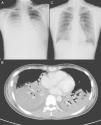

Clinical NotesA previously-healthy 32-year-old woman, a university student, was admitted to the intensive care unit (ICU) of the Taipei Veterans General Hospital, transferred from a local hospital where she had been hospitalized due to four days of high fever, cough with limited sputum production and dyspnea. The patient has never been a smoker, was following no medical treatment of any kind and her previous clinical history showed no relevant disease. Upon admittance, the initial physical examination revealed the presence of respiratory rales in both lung fields, but there was no jugular vein engorgement or any abnormal signs on heart auscultation. The laboratory analysis showed a leukocyte count of 5500/mm3, with 92% neutrophils, 0% bands, and 4% lymphocytes. Sputum Gram staining showed few polymorphonuclear neutrophils, very infrequent epithelial cells and no bacterial or fungal pathogen. Upon arriving at our hospital, the patient presented blood gas with non-rebreather oxygen mask (O2: 15 l/min) with pH=7.49, PaO2=70 mmHg, PCO2=33.5 mmHg, HCO3−=20 mmol/l and O2 saturation=95.7%. The initial chest radiograph taken in our hospital showed diffuse alveolar infiltrates in both lung fields (fig. 1A). All the symptoms and signs met ARDS criteria.

(A) Chest radiography, showing alveolar infiltrates in both lung fields. B) Chest computed tomography, showing diffuse consolidations with air bronchogram in both lower lobes, a subsegmental consolidation in the medial segment of the right middle lobe and minimal pleural effusion. C) After the treatment with inhaled ribavirin, chest radiography revealed an evident resolution of the consolidation in the lower lobes of both lungs.

We performed endotracheal intubation with mechanical ventilation support 4hours after hospitalization due to a very fast deterioration of the patient's respiratory state. After intubation, the patient required a concentration of inspired oxygen of 100%, with positive tele-expiratory pressure of 12 cm H2O, and a tidal volume of 400 ml for proper oxygenation. Thoracic CT showed the presence of diffuse consolidations with air bronchogram in both lower lobes and a subsegmental consolidation in the medial segment of the right middle lobe (fig. 1B). Fiber optic bronchoscopy revealed a small quantity of secretion of the airways in the bronchi of both sides, but there were no other alterations. Staining for bacteria, fungi and tuberculosis, as well as sputum and bronchoalveolar lavage (BAL) liquid cultures all came back negative. Enzyme-linked immunosorbent assay for IgM specific for cytomegalovirus and the simple herpes virus, antibodies and urinary antigen for legionellosis, latex test for serum cryptococcal antigen, antibody technique immunofluorescence for IgM specific for the capsid of the Epstein-Barr virus and IgM for chlamydia, particle agglutination test for the anti-body for Mycoplasma pneumoniae (M. pneumoniae) were al negative. Enzyme immunoassay (EIA) for anti-HIV in serum was also negative. Toluidine blue O stain and polymerase chain reaction testing for cytomegalovirus (CMV-PCR) in BAL liquid were negative, but EIA for the RSV antigen in BAL liquid was intensely positive. Initially, before the diagnosis of the infection by RSV, this patient had been treated with intravenous levofloxacin, imipenem, teicoplanin and methylprednisolone, but no improvement was observed in the clinical signs or symptoms or in the lung infiltrations on chest Rx 7 days after hospitalization. Thus, we administered inhaled ribavirin (Virazole; Ben Venue Laboratory, Inc; Bedford, OH) (6 g en 300 ml of normal physiological serum, continuously for 18hours/day) for three days, beginning on the eighth day after hospitalization. The follow-up chest Rx showed an evident reduction in the consolidation in both lung fields (fig. 1C) and there was a notable improvement in all the clinical signs and symptoms. Due to the severe ARDS, the patient was still not extubated. Fourteen days after hospitalization, the patient was finally and satisfactorily extubated and was later discharged 22 days after admittance with outpatient follow-up and no need for oxygen therapy. At the time of the patient's release, blood gas breathing room air was pH=7.44, PaO2=97 mmHg, PCO2=40 mmHg, HCO3−=27 mmol/l, and O2 saturation=98%. Lung function tests both before and 4 months after discharge were FVC: 79%, DLCO: 55%, DLCO/alveolar volume: 3.35 (66%) and FVC: 104%, DLCO: 72%, DLCO/alveolar volume: 3.93 (77%), respectively. There was no wheezing or dry cough after the discharge. T CD4+ cell count was initially 198/mm3 upon admittance, later recovering and reaching a value of 554/mm3 two months after discharge.